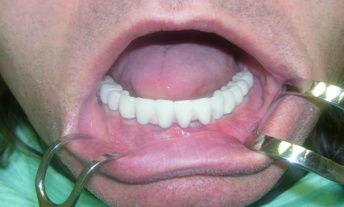

Bezzubá čelist je hlavní indikací pro ošetření pomocí implantátů. Zejména celkové zubní náhrady v dolní čelisti mají velice nízkou stabilitu a držení díky velkému úbytku kosti.

S pomocí zubních implantátů můžeme díky různým kotevním systémům (třmeny, kulové hlavy, Locatory) zajistit stabilitu a držení protézy nebo při použití většího počtu implantátů zhotovit pevné náhrady – můstky nalepené nebo našroubované na pevno na implantáty.

S těmito typy náhrad můžeme dosáhnout perfektní funkci, výbornou estetiku, fonetiku a současně zajistit u pacienta možnost dobré hygienickou péče a čištění, která je pro životnost implantátů velice důležitá.